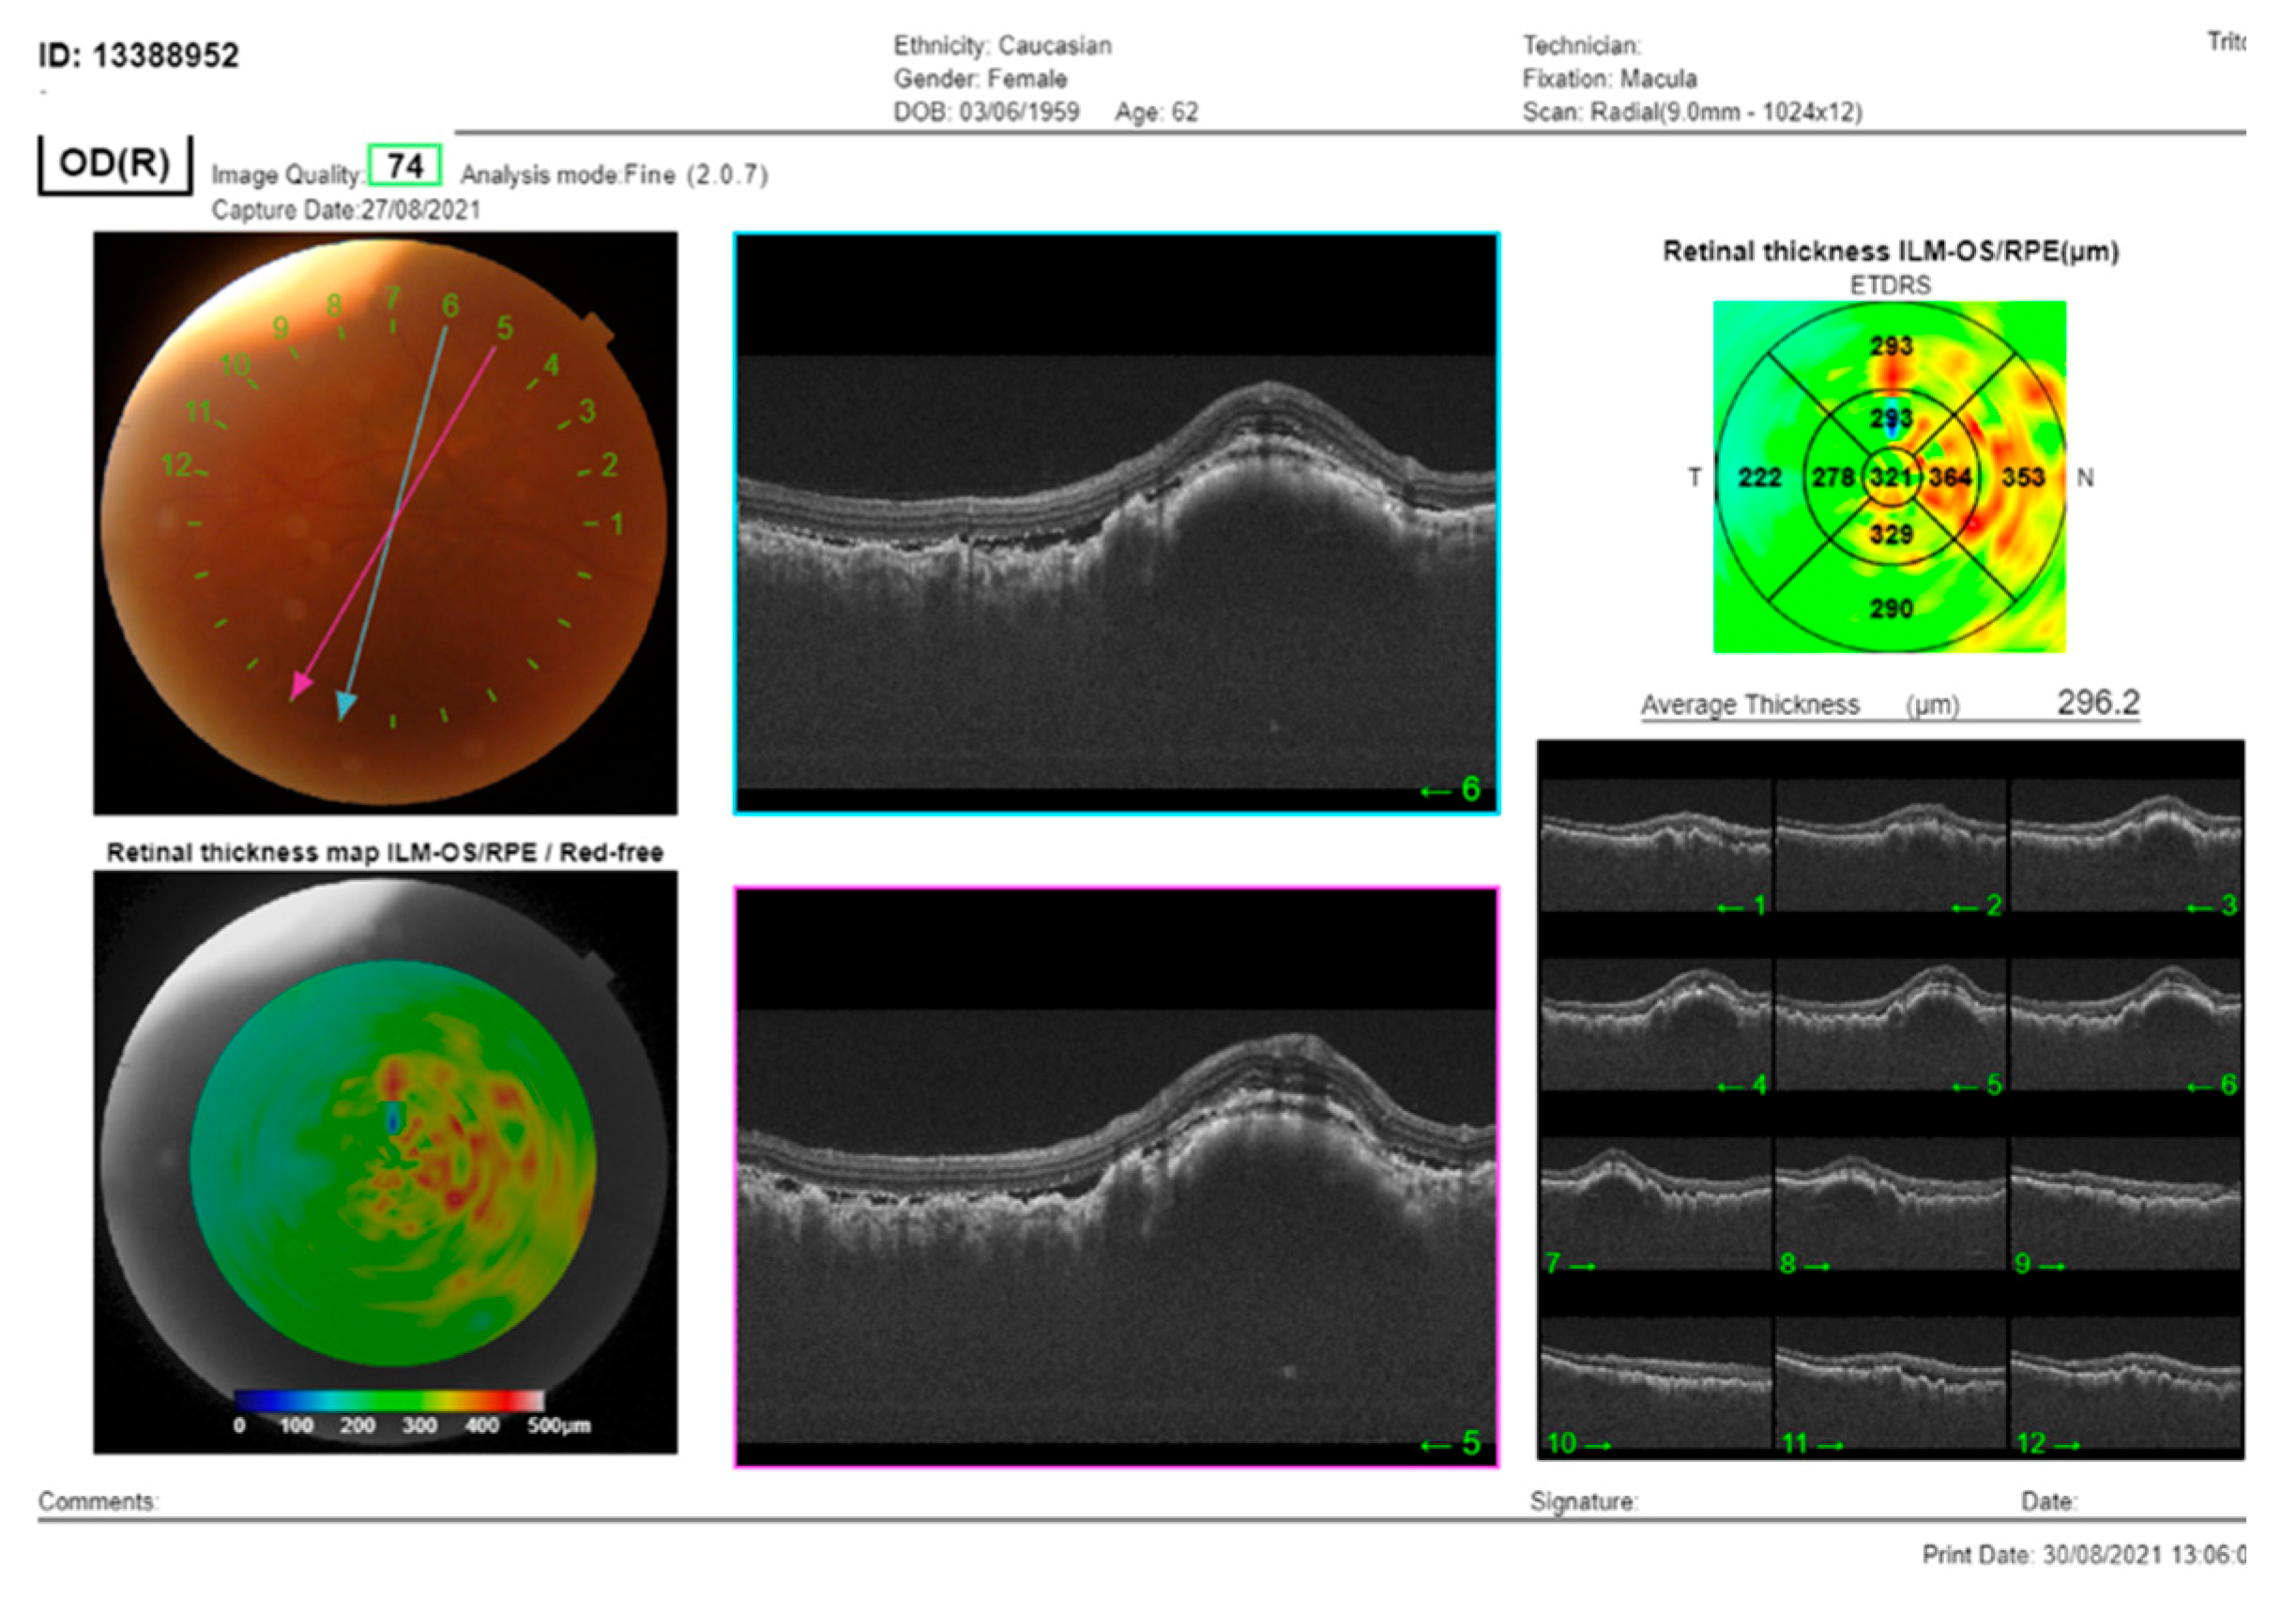

Figure 2. The SS-OCT (DRI OCT Triton, Topcon Co, Tokyo, Japan) showed choroidal thickening with overlying folds and subretinal fluid. OCT of the macula of the RE: cross-section through the lesion showed thickening of the choroid, with subretinal fluid and overlying folds of RPE.